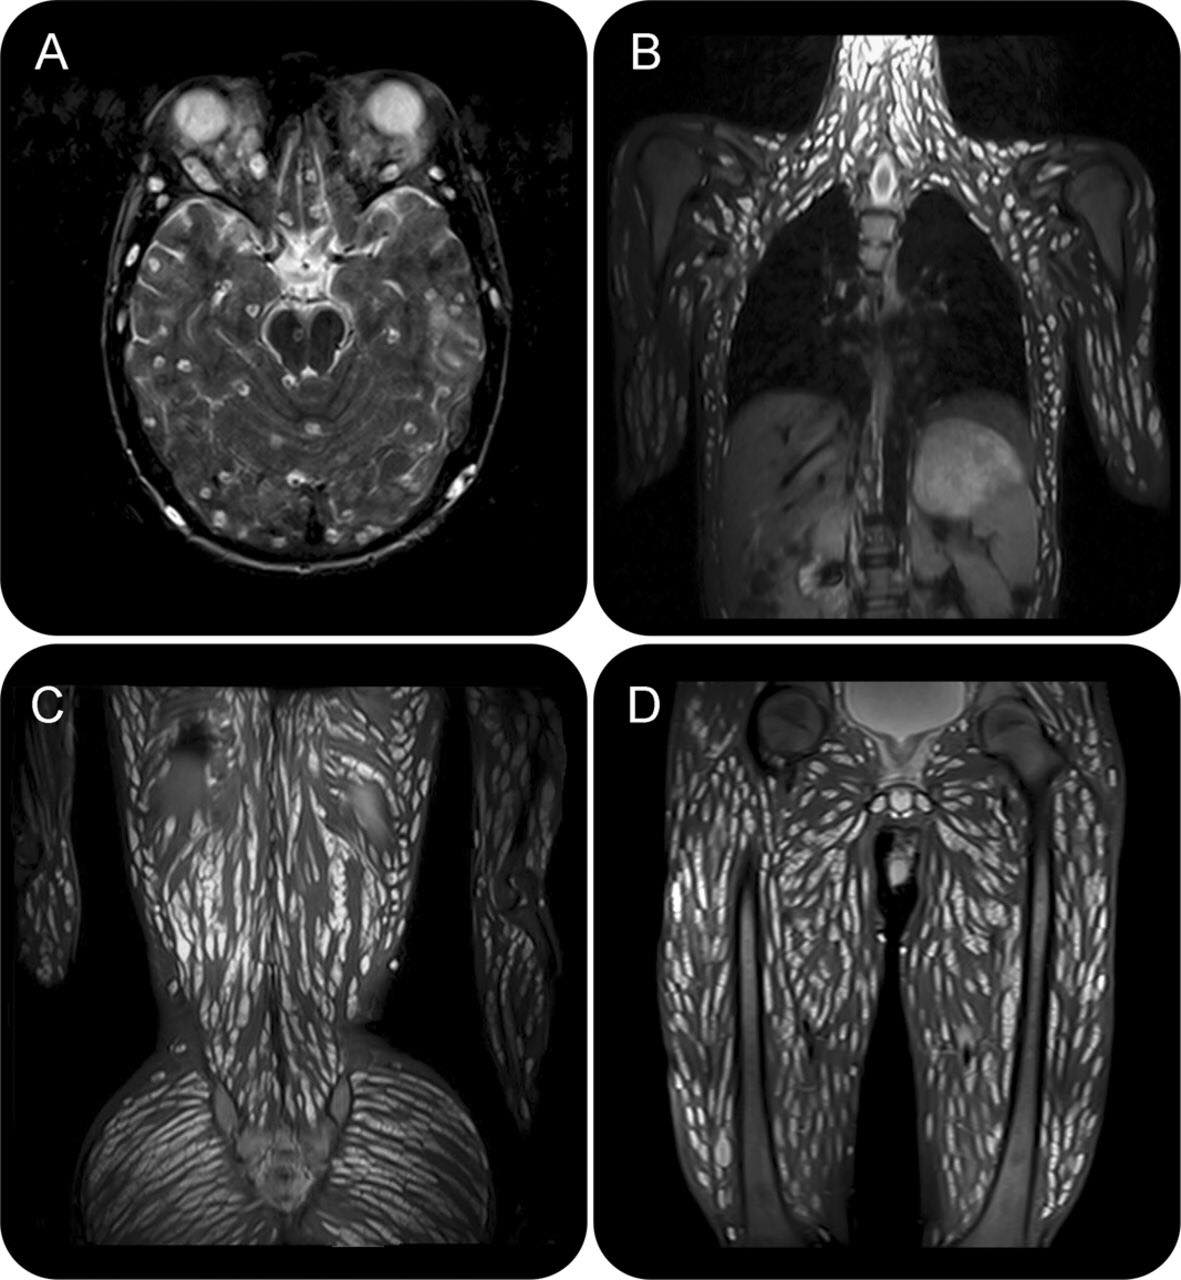

綜合外媒報導,泰國素羅娜麗科技大學醫學院、寄生蟲研究中心(PDRC)於1月12日公布一份病歷資料,記載了一名18歲男子因出現頭痛、嘔吐、抽搐、感官扭曲等不適症狀,緊急就醫診斷。醫生見狀立即替男子進行檢查,怎料發現其體內不論是腦部、胸腹部、脊椎、四肢都長滿豬肉絛蟲,整個影像看起來相當恐怖。

醫生指出,男子罹患豬囊尾蚴病(又稱囊蟲病),初步推測他誤食半生不熟的豬肉,或附有蟲卵的食物或水源,另也有可能是進食前沒有先洗手導致。所幸經過一連串的驅蟲藥、類固醇、抗癲癇藥物治療與控制後,男子情況已明顯好轉。